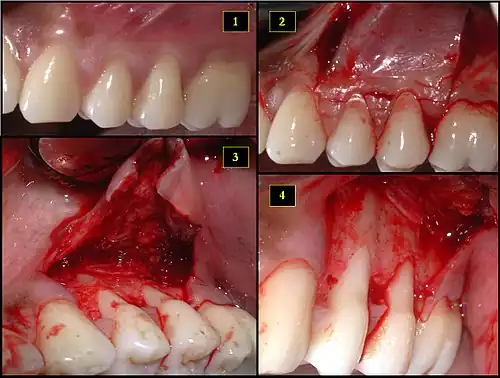

1. Recipient site exhibits gingival recession on both premolars and first molar (molar recession is not an esthetic issue and will not be treated)

2. Incisions prior to flap reflection

3. Full thickness flap elevated

4. Another viewpoint of the flapped recipient site